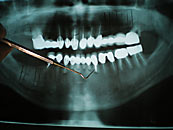

Röntgenbild eines Gebisses